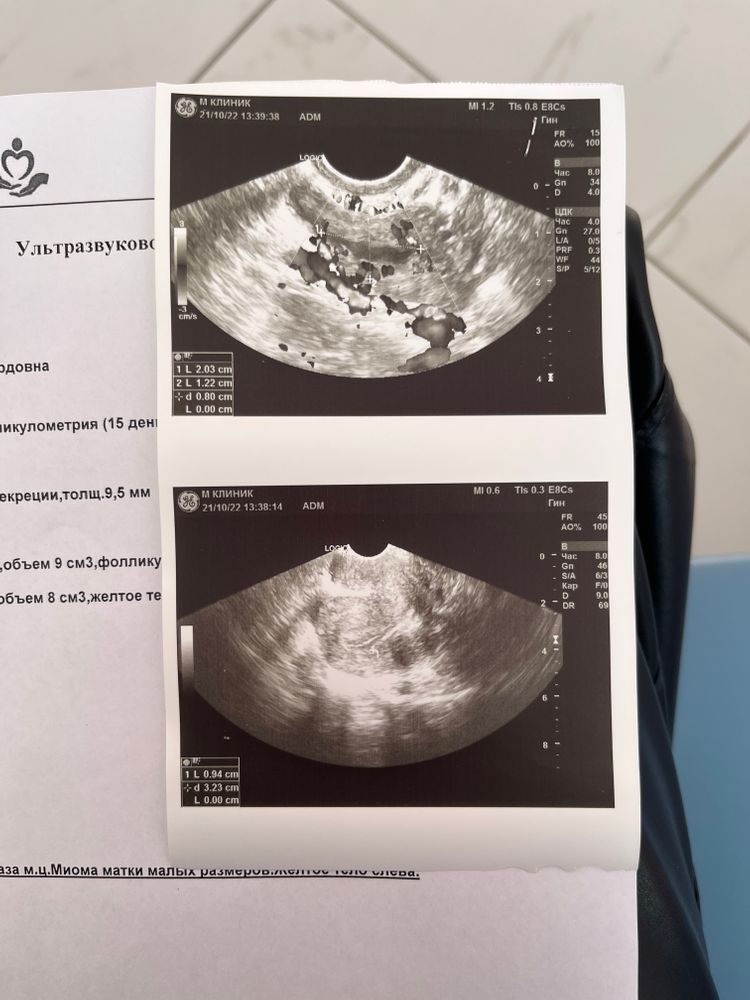

15 дц. Узи после вми.

Нормальные ли анализы? Выход укола хгч 5000 ВМИ ИИ